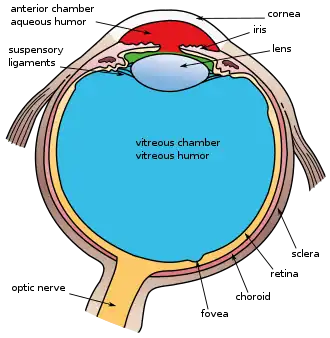

The eye can be considered as a living optical device. It is approximately spherical in shape, with its outer layers, such as the outermost, white part of the eye (the sclera) and one of its inner layers (the pigmented choroid) keeping the eye essentially light tight except on the eye's optic axis. In order, along the optic axis, the optical components consist of a first lens (the cornea—the clear part of the eye) that accounts for most of the optical power of the eye and accomplishes most of the focusing of light from the outside world; then an aperture (the pupil) in a diaphragm (the iris—the coloured part of the eye) that controls the amount of light entering the interior of the eye; then another lens (the crystalline lens) that accomplishes the remaining focusing of light into images; and finally a light-sensitive part of the eye (the retina), where the images fall and are processed. The retina makes a connection to the brain via the optic nerve. The remaining components of the eye keep it in its required shape, nourish and maintain it, and protect it.

The eye is not shaped like a perfect sphere; rather it is a fused two-piece unit, composed of an anterior (front) segment and the posterior (back) segment. The anterior segment is made up of the cornea, iris and lens. The cornea is transparent and more curved and is linked to the larger posterior segment, composed of the vitreous, retina, choroid and the outer white shell called the sclera. The cornea is typically about 11.5 mm (0.45 in) in diameter, and 0.5 mm (500 μm) in thickness near its centre. The posterior chamber constitutes the remaining five-sixths; its diameter is typically about 24 mm (0.94 in). An area termed the limbus connects the cornea and sclera. The iris is the pigmented circular structure concentrically surrounding the centre of the eye, the pupil, which appears to be black. The size of the pupil, which controls the amount of light entering the eye, is adjusted by the iris' dilator and sphincter muscles.

The eye is made up of three coats, or layers, enclosing various anatomical structures. The outermost layer, known as the fibrous tunic, is composed of the cornea and sclera, which provide shape to the eye and support the deeper structures. The middle layer, known as the vascular tunic or uvea, consists of the choroid, ciliary body, pigmented epithelium and iris. The innermost is the retina, which gets its oxygenation from the blood vessels of the choroid (posteriorly) as well as the retinal vessels (anteriorly).

The spaces of the eye are filled with the aqueous humour anteriorly, between the cornea and lens, and the vitreous body, a jelly-like substance, behind the lens, filling the entire posterior cavity. The aqueous humour is a clear watery fluid that is contained in two areas: the anterior chamber between the cornea and the iris, and the posterior chamber between the iris and the lens. The lens is suspended to the ciliary body by the suspensory ligament (zonule of Zinn), made up of hundreds of fine transparent fibers which transmit muscular forces to change the shape of the lens for accommodation (focusing). The vitreous body is a clear substance composed of water and proteins, which give it a jelly-like and sticky composition.[6]